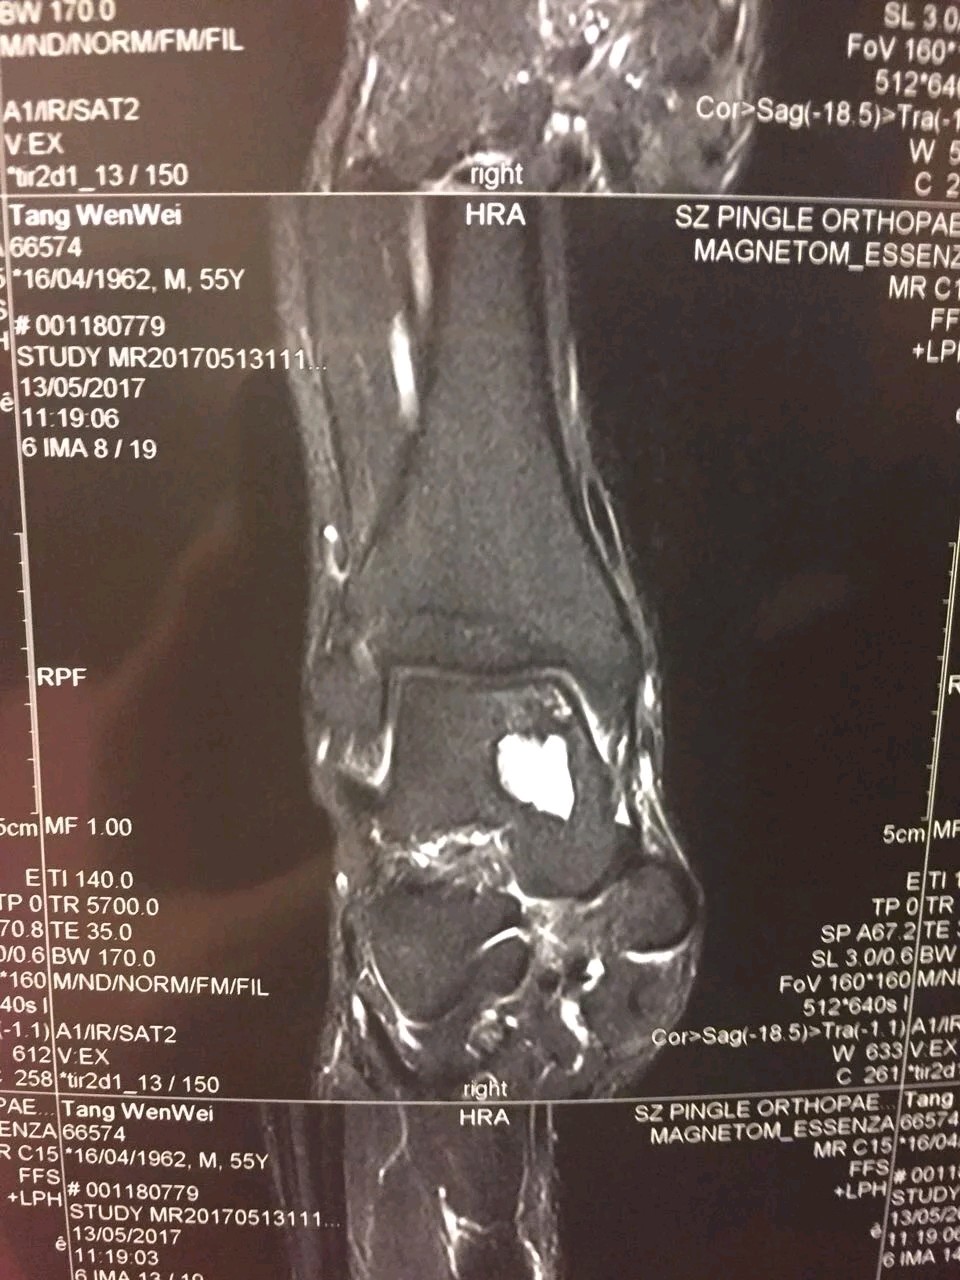

我们从发生在前两周的一个病例说起。那是我每周四的普通门诊,一个22岁的年轻小伙,一瘸一拐的走了进来,第一句话就是:医生我脚又崴了。这种主诉对我而言已经习以为常,但是,他接下来的话让我对他的病情感到担忧。他告诉我,在5年前打篮球时第一次扭伤踝关节,当时并没有去看医生,只是在家休养几天,自认为痊愈之后,继续进行高强度篮球运动。但是,平时运动后总会感踝关节疼痛不适,最重要的是他自己都不记得后面再次崴伤过多少次。经过详细的查体和影像学检查,印证了我的担忧。他的踝关节外侧副韧带撕裂,严重骨质增生,最致命的是踝关节软骨大面积重度损伤。通俗而言就是我们称之的关节退变。不可想象一个刚步入才花样年华的小伙,踝关节却以进入古稀之年。数年后面对他的很可能是踝关节融合或者关节置换。这就是实实在在的例子,它告诉我们:请关爱自己的脚踝。